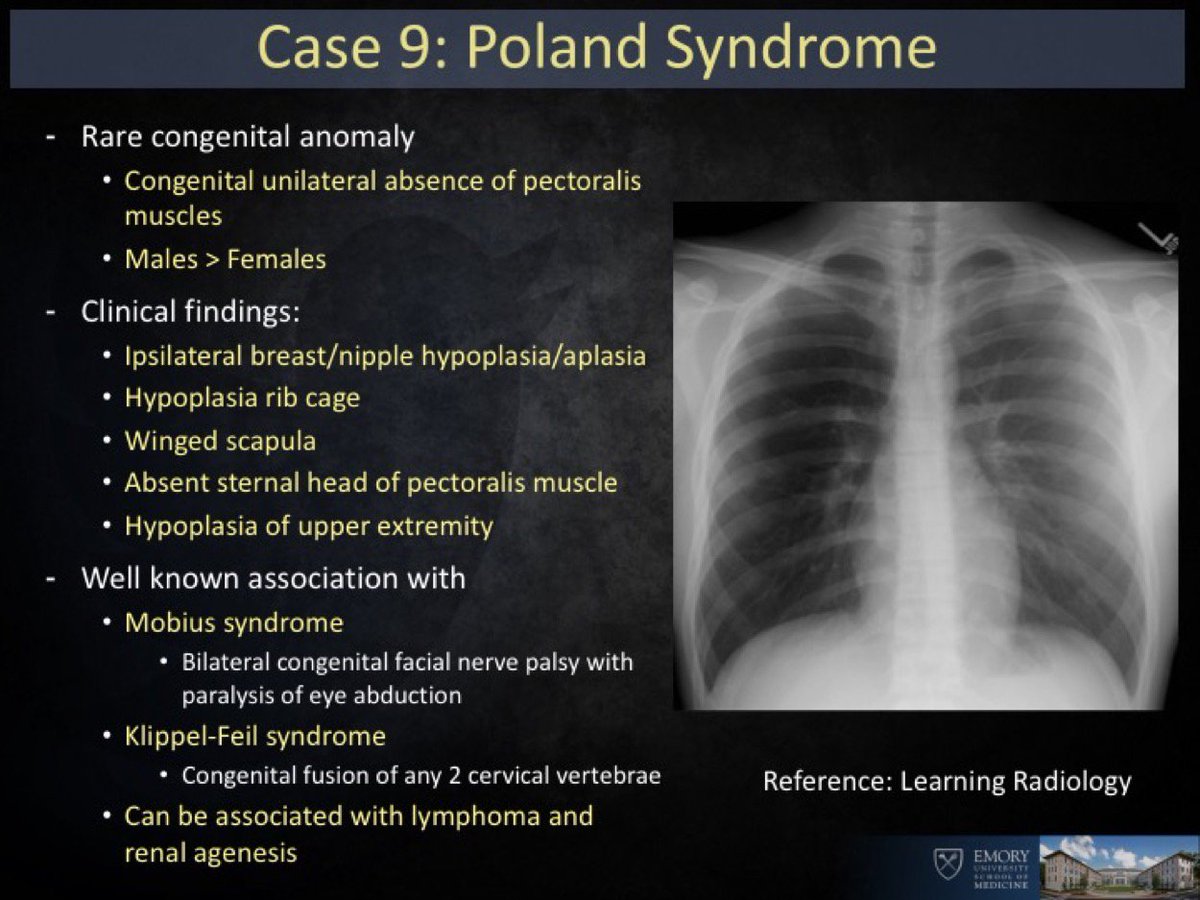

LearningRadiology - Poland, Syndrome

learningradiology.comsyndrome poland learningradiology here arrows left muscle same without click

Poland Syndrome – Radiology Cases

radiologycases.myPoland Syndrome - Stock Image - C021/1675 - Science Photo Library

radiologycases.myPoland Syndrome - Stock Image - C021/1675 - Science Photo Library